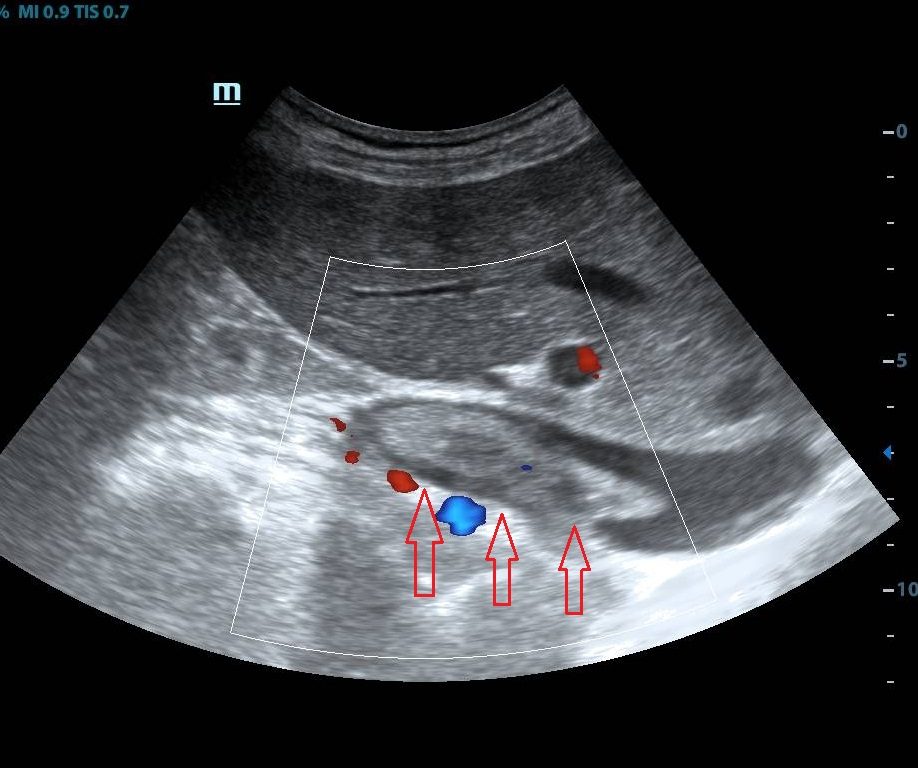

Интраоперационные данные. Продольным разрезом вскрыт легочный ствол, поперечным разрезом вскрыта правая легочная артерия, выполнена ревизия. Левая легочная артерия и ее ветви свободно проходимы. Правая легочная артерия полностью окклюзирована опухолевым тромбом.Из правой легочной артерии и долевых ветвей удалены опухолевые тромбы различной степени плотности. Проведена профилактика материальной эмболии. Ствол правой легочной артерии ушит непрерывным обвивным швом нитью пролен 5/0. Окончание ИК. Выполнена деканюляция. Гепарин нейтрализован расчетной ½ дозой протамина сульфата. Полная срединная лапаротомия. При ревизии выявлено новообразование правой почки в нижнем полюсе, ближе к воротам размером 7х6х6 см с неокклюзирующим тромбозом супраренального и позадипеченочного отдела НПВ. Произведен доступ к НПВ через правый боковой канал. Острым и тупым путем выделена НПВ в инфраренальном отделе, супраренальном отделе (с пораженными паракавальными лимфоузлами), в позадипеченочном и поддиафрагмальном отделах НПВ. Произведена мобилизация печени, мобилизация коротких печеночных вен, медиальная ротация печени. Выделена правая почка с правым надпочечником таким образом, чтобы препарат остался фиксирован к НПВ на пораженной правой почечной вене. Осуществлена тотальная сосудистая изоляция печени (пережатие НПВ и ее притоков, печеночно-двенадцатиперстной связки). Продольным разрезом 8 см от устья правой почечной вены выполненакаватомия в супраренальном отделе. Из просвета удален флотирующий опухолевый тромб размером 7х2х1,5 см (рис. 4). Произведена резекция устья правой почечной вены и НПВ с учетом поражения 1/3 полуокружности НПВ. Каватомное отверстие ушито проленом 3/0 непрерывным швом. Препарат удален единым блоком. Общее время операции составило 290 мин, время ИК — 80 мин, время пережатия аорты —59 мин. Кровопотеря составила 200 мл.

Рис. 4.Интраоперационное фото. Этап удаления опухолевого тромба из нижней полой вены у пациента Г.